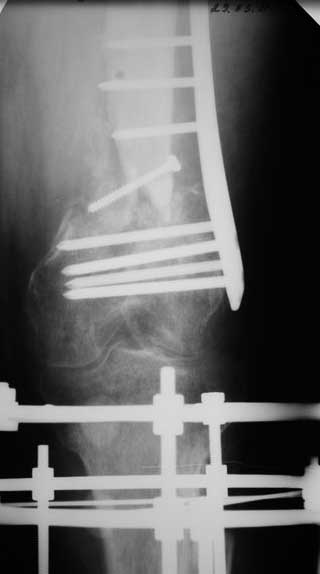

Уважаемые коллеги. Хотелось бы услышать Ваше мнение по следующему случаю. На лечении в отделении находится пациент 45 лет. С диагнозом: Замедленно консолидирующийся надмыщелковый перелом левой бедренной кости фиксированный пластиной от 06.12.10. Ложный сустав большеберцовой кости левой голени фиксированный АНФ от 06.12.10.

Анамнез: травма 18.06.10 в результате ДТП, водитель. Диагноз: Сочетанная травма головы, конечностей. ЗЧМТ. Сотрясение головного мозга. Открытый многооскольчатый внутрисуставной перелом мыщелков и нижней трети левой бедренной кости со смещением отломков. Открытый перелом костей левой голени в верхней трети со смещением отломков. Обширные рвано – ушибленные раны левого бедра, верхней трети левой голени. Находился на лечении в нескольких стационарах, где проводились оперативные вмешательства.

7. 06.12.2010г. Открытая репозиция, остеосинтез чрезмыщеково – надмыщелкого перелома левой бедренной кости пластиной со свободной костной пластикой из гребня левой подвздошной кости (во время операции из за сомнений в жизнеспособности костного отломка перелома бедра произведено его удаление. За счет чего образовался дефект костной ткани и укорочение левого бедра на 5,0 см; Мыщелки бедра были в сгибание, 5 месяцев нога не опорная, при попытке их репонировать крошились , зафиксировали как стояли. Остеосинтез переломов костей левой голени в АНФ.

Местно: Ходит при помощи костылей с попыткой полной нагрузки на левую ногу. Левый коленный сустав в положении разгибания. Движения в коленном суставе качательные. Воспалительных явлений области послеоперационных рубцов, мест выхода спиц нет. Анализы крови без воспалительной реакции.

Голень: выполнить остеосинтез левой большеберцовой кости интрамедуллярным стержнем с рассверливанием. На основании боковой рентгенограммы коленного сустава мыщелки бедра в сгибании, голень в переднем подвывихе, создается впечатление, что удастся завести стержень при такой контрактуре, или выполнить отсечение бугристости, попытаться согнуть колено и заштифтовать. Есть ли опыт штифтования при стойких контрактурах?